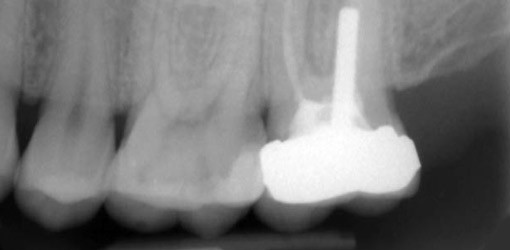

Stiftversorgungen

Bei Revisionsbehandlungen wird häufig die Entfernung eines Stiftes notwendig. Zeigen sich im Röntgenbild laterale Aufhellungen im Stiftbereich, besteht der Verdacht einer Perforation.

Die Beurteilung von Perforationen ist besonders bei Oberkiefermolaren sehr schwierig, da in diesen Fällen eine eventuelle Perforation in der Trifurkation oder der palatinalen Wurzel durch die Wurzelkontur überlagert wird (Abb. 9a).

Behandlungsplanung

Zunächst sollte das Risiko einer Fraktur der durch den Stift geschwächten Wurzel abgeschätzt werden und der Nutzen des Erhalts des Zahnes geprüft werden.

Wurzelstifte lassen sich mit modernen Behandlungstechniken in der Regel gut entfernen, die Prognose ist daher meist positiv zu beurteilen (Abb. 9b–c).